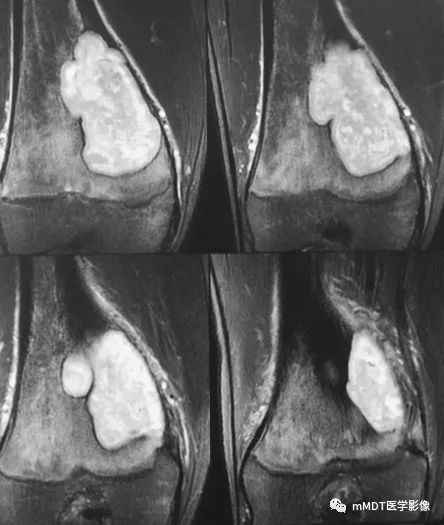

MRI冠状面脂肪抑制序列

CT见病变位于股骨远端干骺端,呈分叶状、偏心膨胀性生长,密度欠均匀,整体低于肌肉密度,部分区域密度接近水,其内可见点状、线状、弧形、圆形的高密度影,大部分边缘硬化,局部深侵蚀骨内膜,局部骨壳不完整。MR上,T1WI信号略低于肌肉,T2压脂呈现不均匀高信号,未见明确软骨小叶结构及纤维分隔,周围可见水肿。

最后看软骨粘液样纤维瘤,好发年龄为10-30岁,好发位置为长骨干骺端,表现为偏心膨胀性生长,边缘清晰,10%可见钙化,骨皮质可不连续。MR呈现软骨及粘液成分特点,T2WI为高信号,与本例相符。因此,结合患者年龄及病变位置,首先考虑软骨粘液样纤维瘤,低级别软骨肉瘤不完全除外。